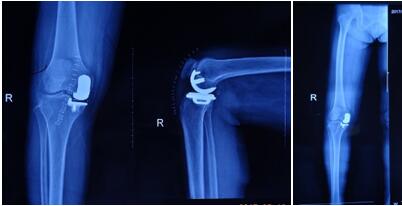

近日骨科在張富軍主任帶領(lǐng)下,在保膝理念的驅(qū)動(dòng)下,成功開展我院首例生物單髁膝關(guān)節(jié)置換術(shù),更是全國第9例,西北地區(qū)第2例。這意味著本次手術(shù)在西安市內(nèi)乃至整個(gè)西北地區(qū)都極為罕見,我院在骨關(guān)節(jié)病診治技術(shù)邁上了新的臺(tái)階,為膝關(guān)節(jié)炎患者提供了一種新的選擇。

提起膝關(guān)節(jié)置換術(shù),多數(shù)病人起初都是拒絕的,至少在單髁置換術(shù)出現(xiàn)之前,不乏有“談虎色變”的患者,而這些患者普遍遺留這樣一個(gè)問題:能否僅置換部分磨損的關(guān)節(jié),保留大部分自體關(guān)節(jié),用更小的創(chuàng)傷解決痛苦呢?答案是肯定的,隨著科技的進(jìn)步和手術(shù)技術(shù)的精湛,單髁關(guān)節(jié)置換應(yīng)運(yùn)而生,成為近2年風(fēng)靡一時(shí)的手術(shù)方式,術(shù)中要求精確至1mm,其具有創(chuàng)傷小,恢復(fù)快,骨長入理想,骨質(zhì)保留量大,本體感覺不破壞的優(yōu)勢。目前膝關(guān)節(jié)單髁置換多為骨水泥型,生物型全國僅開展9例。生物型作為全新的置換方式比骨水泥型更具有突出的優(yōu)勢,逐漸成為新的趨勢。